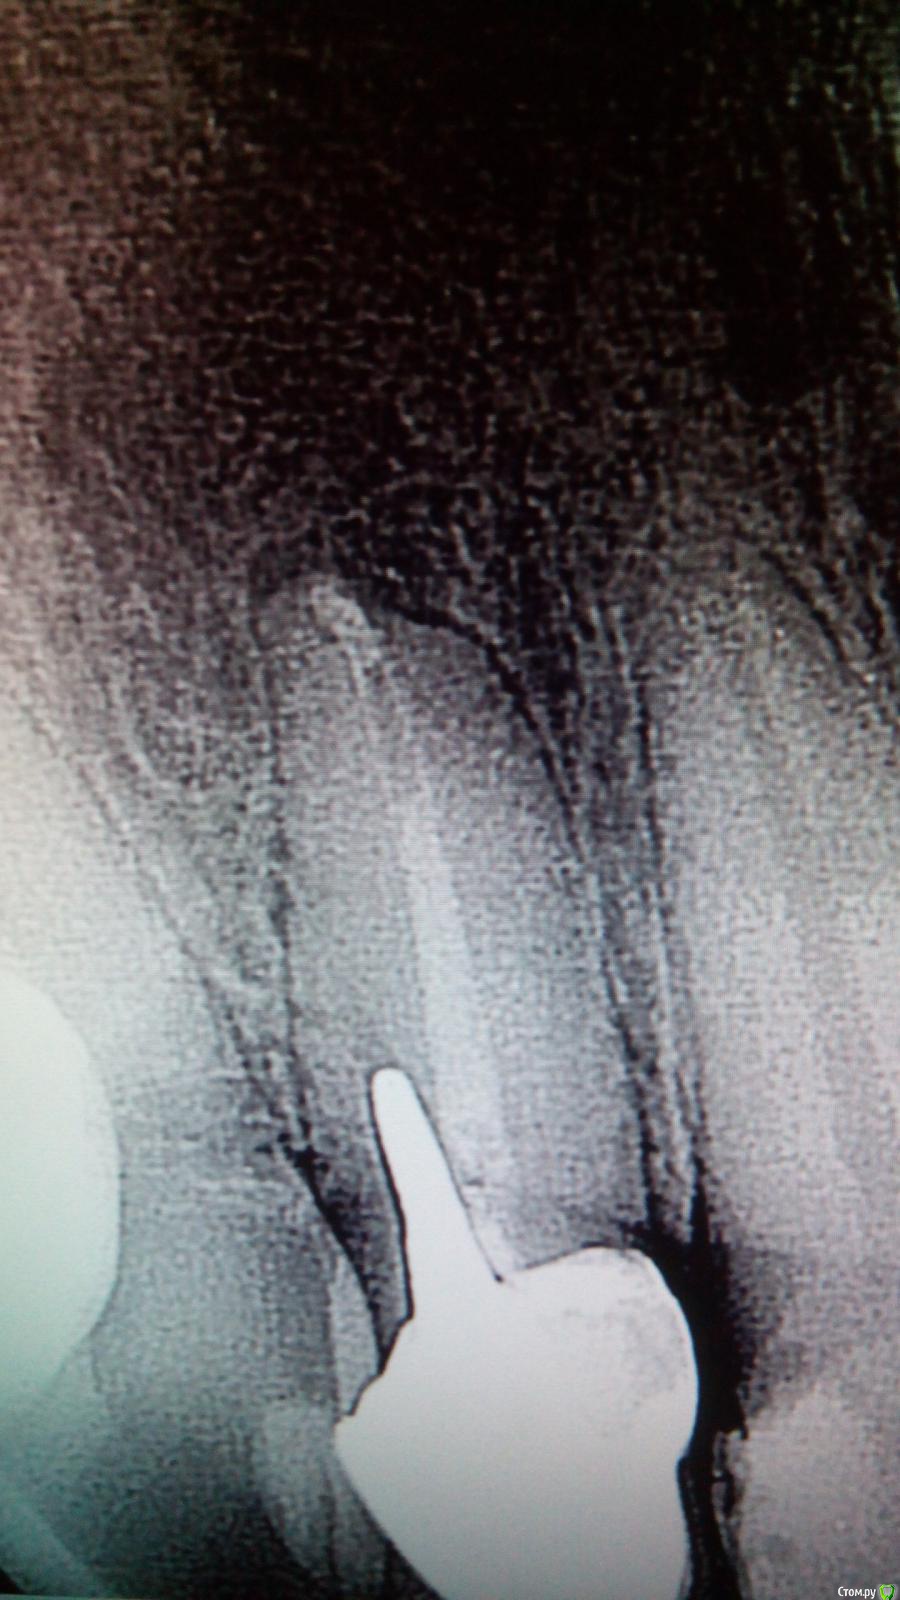

Sveta B Опубликовано 12 февраля, 2015 Поделиться Опубликовано 12 февраля, 2015 Доброго времени суток, коллеги! Помогите советом!12 зуб. Обратился с жалобой на расцементировку конструкции. На снимке: перфорация по ходу распломбировки под штифтово-культевую вкладку+обширное разрежение кости, захватывающее 12 и 11 зубы. Подвижности нет, болей нет. Ко мне пациент попал от ортопеда с целью лечения периодонтита 12 и подготовки под новую штифтово-культевую с коронкой.В другой клинике пациенту настоятельно рекомендовали резекцию.Если кто-нибудь сталкивался с более-менее успешным терапевтическим лечением, поделитесь опытом, пожалуйста! Ссылка на комментарий

shia777 Опубликовано 12 февраля, 2015 Поделиться Опубликовано 12 февраля, 2015 (изменено) Добрый день, у нас в своё время была работа по сложнее, занимались ради науки, по итогу спасли. Был премаляр 4-5 счас уже не помню ситуация была в разы хуже,,, перфо бало на уровне середины корня сделано шаровидным бором, решали так: терапевтическая часть -пломбировка канала цементом для закрытия перфораций (Прорут) перфо в корневой части, хирургическая часть -откидывался лоскут, производилась чистка кисты, которая имелась на тот момент,затем мембрана и всё закрывалось, ждали от 3-5 месяцев после чего культевая вкладка и коронка,,,,,пациента наблюдали порядка 3-х лет после чего он уехал за бугор))) . В данном случае мне кажется всё не так плохо, резорбции костной ткани в области перфо практически нет,(костные балки сохранены, ренгенологически плотность к.ткани в этой области практически не изменилась) костный сосочек так же цел, что также крайне хорошо ! Удалять его, считаю,не нужно это никогда не поздно сделать, если есть желание пациента и врача то нужно заниматься, тем более что клиническая картина крайне благоприятная. Как было описано в первом случае, нужно перепломбировать канал зуба,потому,как есть воспалительный процесс на верхушке, плотность материала в области верхушки корня и кистогранулёма требуют незамедлительного вмешательства, также чистить канал перфо, обрабатывать, сушить, пломбировать, затем наблюдать клинически и рентгенологически, затем вкладка и коронка,,,всё просто как божий день…..P.S. Крайне важно учесть плотность контактов между соседними зубами. Изменено 12 февраля, 2015 пользователем shia777 Ссылка на комментарий

shia777 Опубликовано 12 февраля, 2015 Поделиться Опубликовано 12 февраля, 2015 (изменено) Относительно планов по резекции верхушки,,,, 50/50 резорбция верхушки есть,незначительная, но есть, границы гранулёмы так же сформированы, но и структура костной ткани в её области пока прослеживается,(желательно видеть Rg в живую) что говорит о реактивности процесса, вариантов лечения таких ситуаций на сегодняшний день, думаю, у любого грамотного терапевта, как минимум пару тройку найдётся, на 2-3 месяца, но это того стоит, так что с резекцией,думаю,можно не торопиться, но замечу, что и не исключается, мы в таких случаях тактику ведения решаем коллегиально терапевт-хирург-ортопед.И конечно же нужно понимать, что в каждом случае тактика ведения пациента крайне индивидуальна !!! Изменено 12 февраля, 2015 пользователем shia777 Ссылка на комментарий